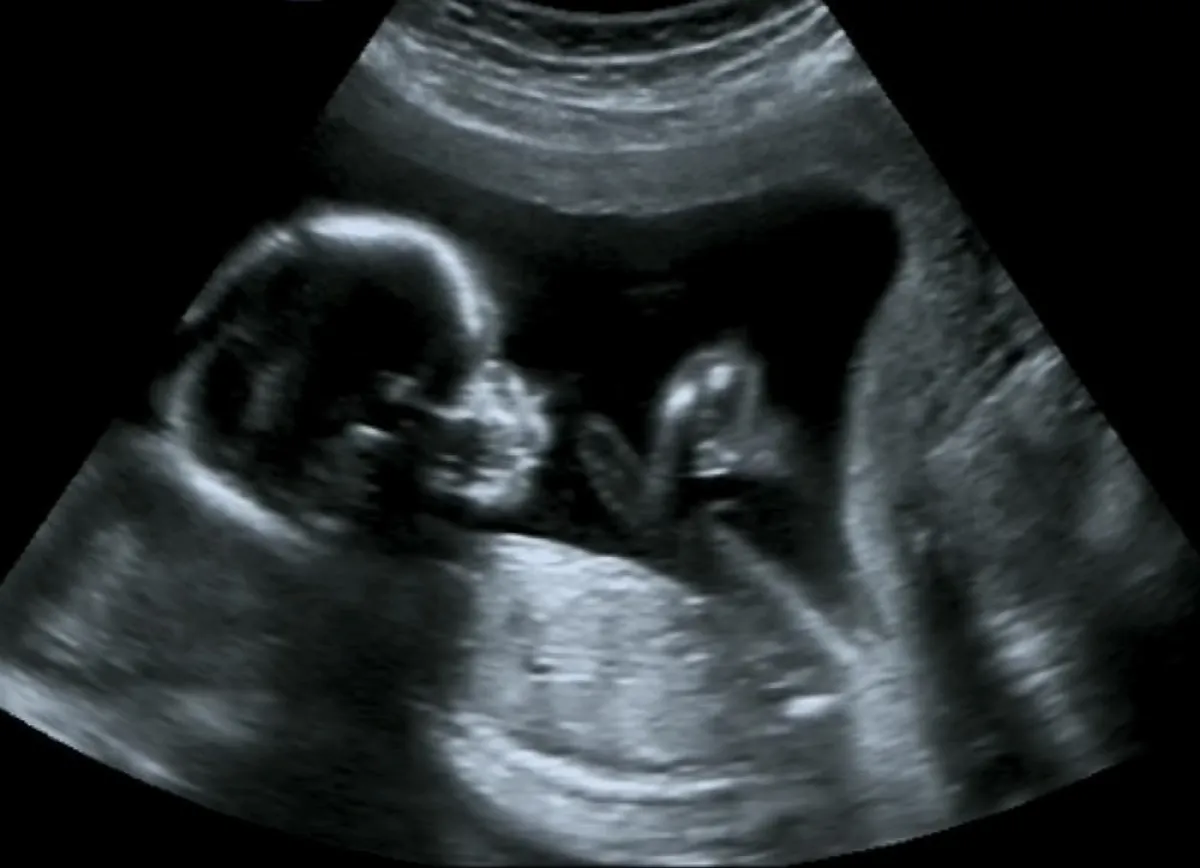

في الشهر الرابع من الحمل يكون قد أصبح وزن جنينك حوالي 5 أونصات وأصبح طوله حوالي 14سم، والآن تفكرين ماذا سيأكل هذا الصغير، لكي يخرج إلى الحياة سليمًا ومعافى وبلا إعاقات ويتمتع ببنية قوية، وكذلك قدرات عقلية مميزة.